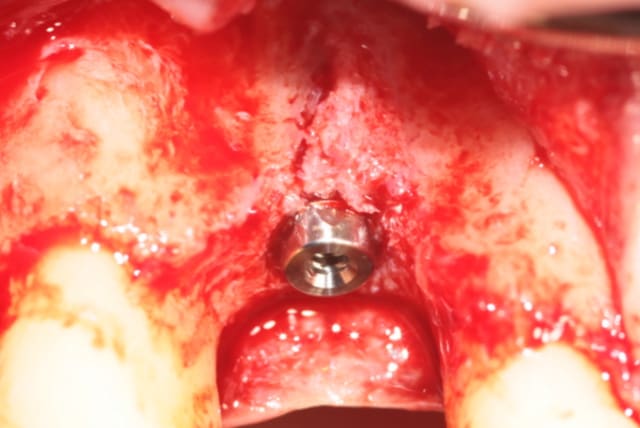

Extraction implantation immédiate mais il y a au moins 7 spires à nue... (photo 1, 2)

dans cette technique un pilier de 2mm de haut est vissé sur l'implant, ce pilier contient un orifice qui permet de transfixer la barre (photo 3,4)